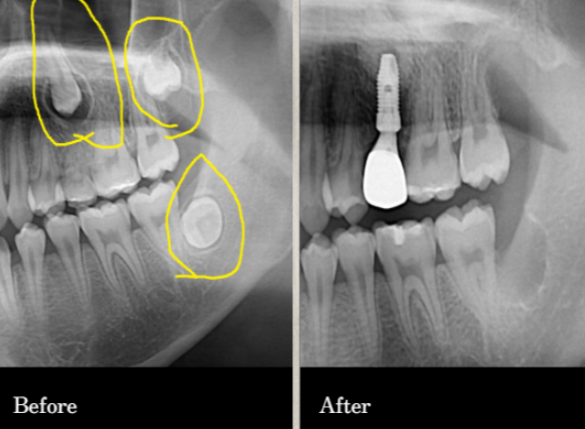

수많은 환자의 경험과 신뢰로 증명된

연세원치과 사랑니 발치입니다.

*위 케이스는 본원에서 진행 받으신 분의 동의 후 동일한 촬영 조건에서 촬영한 사진을 사용하였습니다.